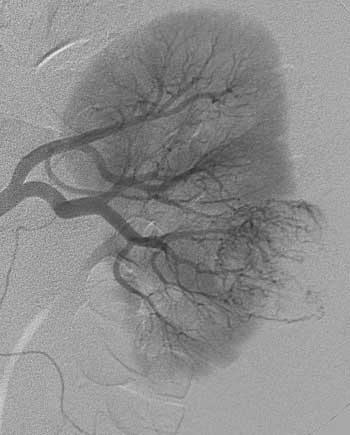

Рис. 4. Рак левой почки. T3aN0M0. Опухоль IV типа васкуляризации. Мелкие опухолевые сосуды неравномерно распре-делены по площади опухоли.